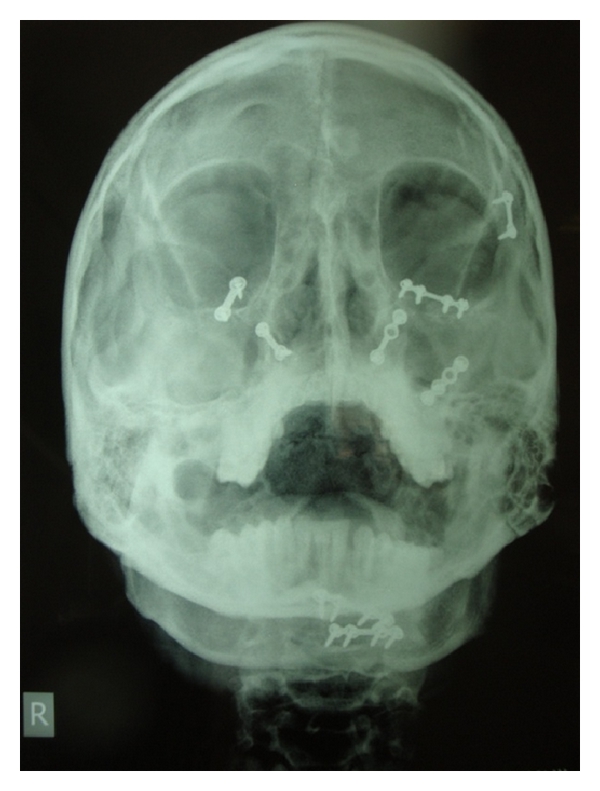

On arrival, his vitals were stable. He was fully conscious, well oriented with time, place, and person. Computed tomography scan was advised, and neurological complications were ruled out. Computed tomography images revealed mandibular left parasymphysis fracture, bilateral Lefort II fractures with comminuted anterior, medial and posterior walls of maxilla (Figures 1 and 2). The right zygoma was downwardly rotated and displaced, and bilateral infraorbital rim fractures were present.

Open reduction and rigid internal fixation of the maxillofacial fractures were achieved by using miniplates osteosynthesis under general anesthesia by submental intubation. Postoperative healing was uneventful. Aesthetically pleasing and functionally acceptable result was obtained. On one-year followup, there was no evidence of any complications (Figures 3 and 4).